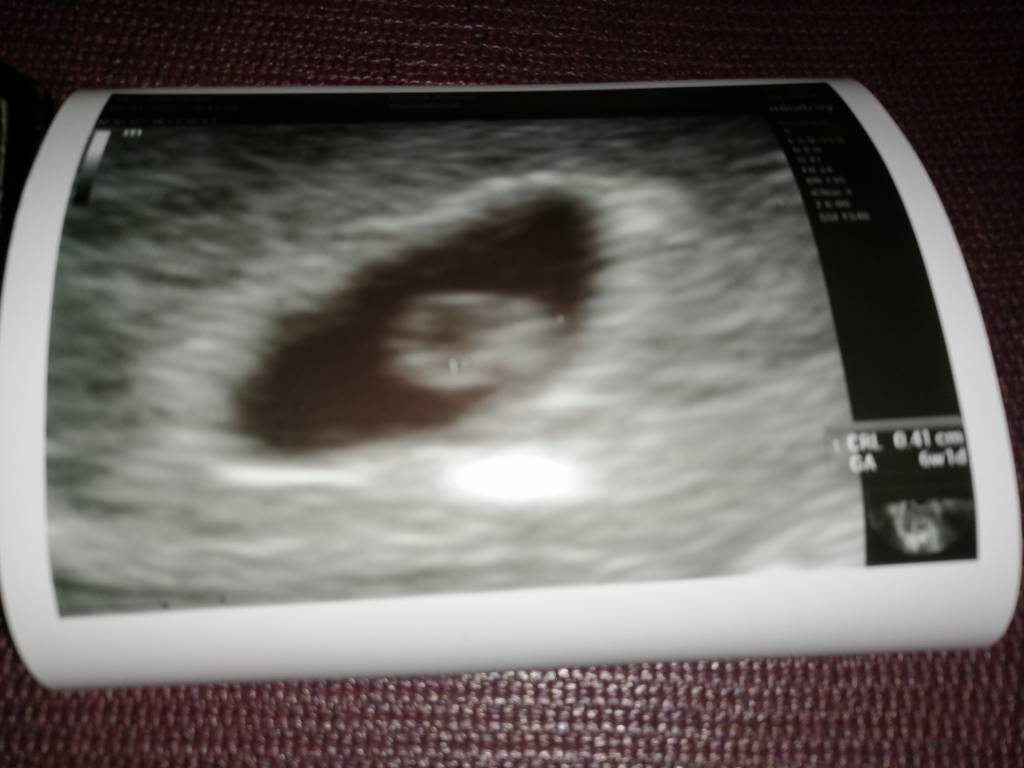

Miałam podobny widok i parametry 30.12Ja juz po, Fasolka ma 0,41cm, 6+1, biło serduszko, nie chciał jeszcze puszczać, ale widziałam jak pięknie pulsowało [emoji3059][emoji3059] mówił, że zarodek dobrze, wysoko zagnieżdżony [emoji3059] ale się cieszę [emoji3059]Zobacz załącznik 1223035

Gratulacje.. To teraz kiedy na kolejną idziesz.??Ja juz po, Fasolka ma 0,41cm, 6+1, biło serduszko, nie chciał jeszcze puszczać, ale widziałam jak pięknie pulsowało [emoji3059][emoji3059] mówił, że zarodek dobrze, wysoko zagnieżdżony [emoji3059] ale się cieszę [emoji3059]Zobacz załącznik 1223035